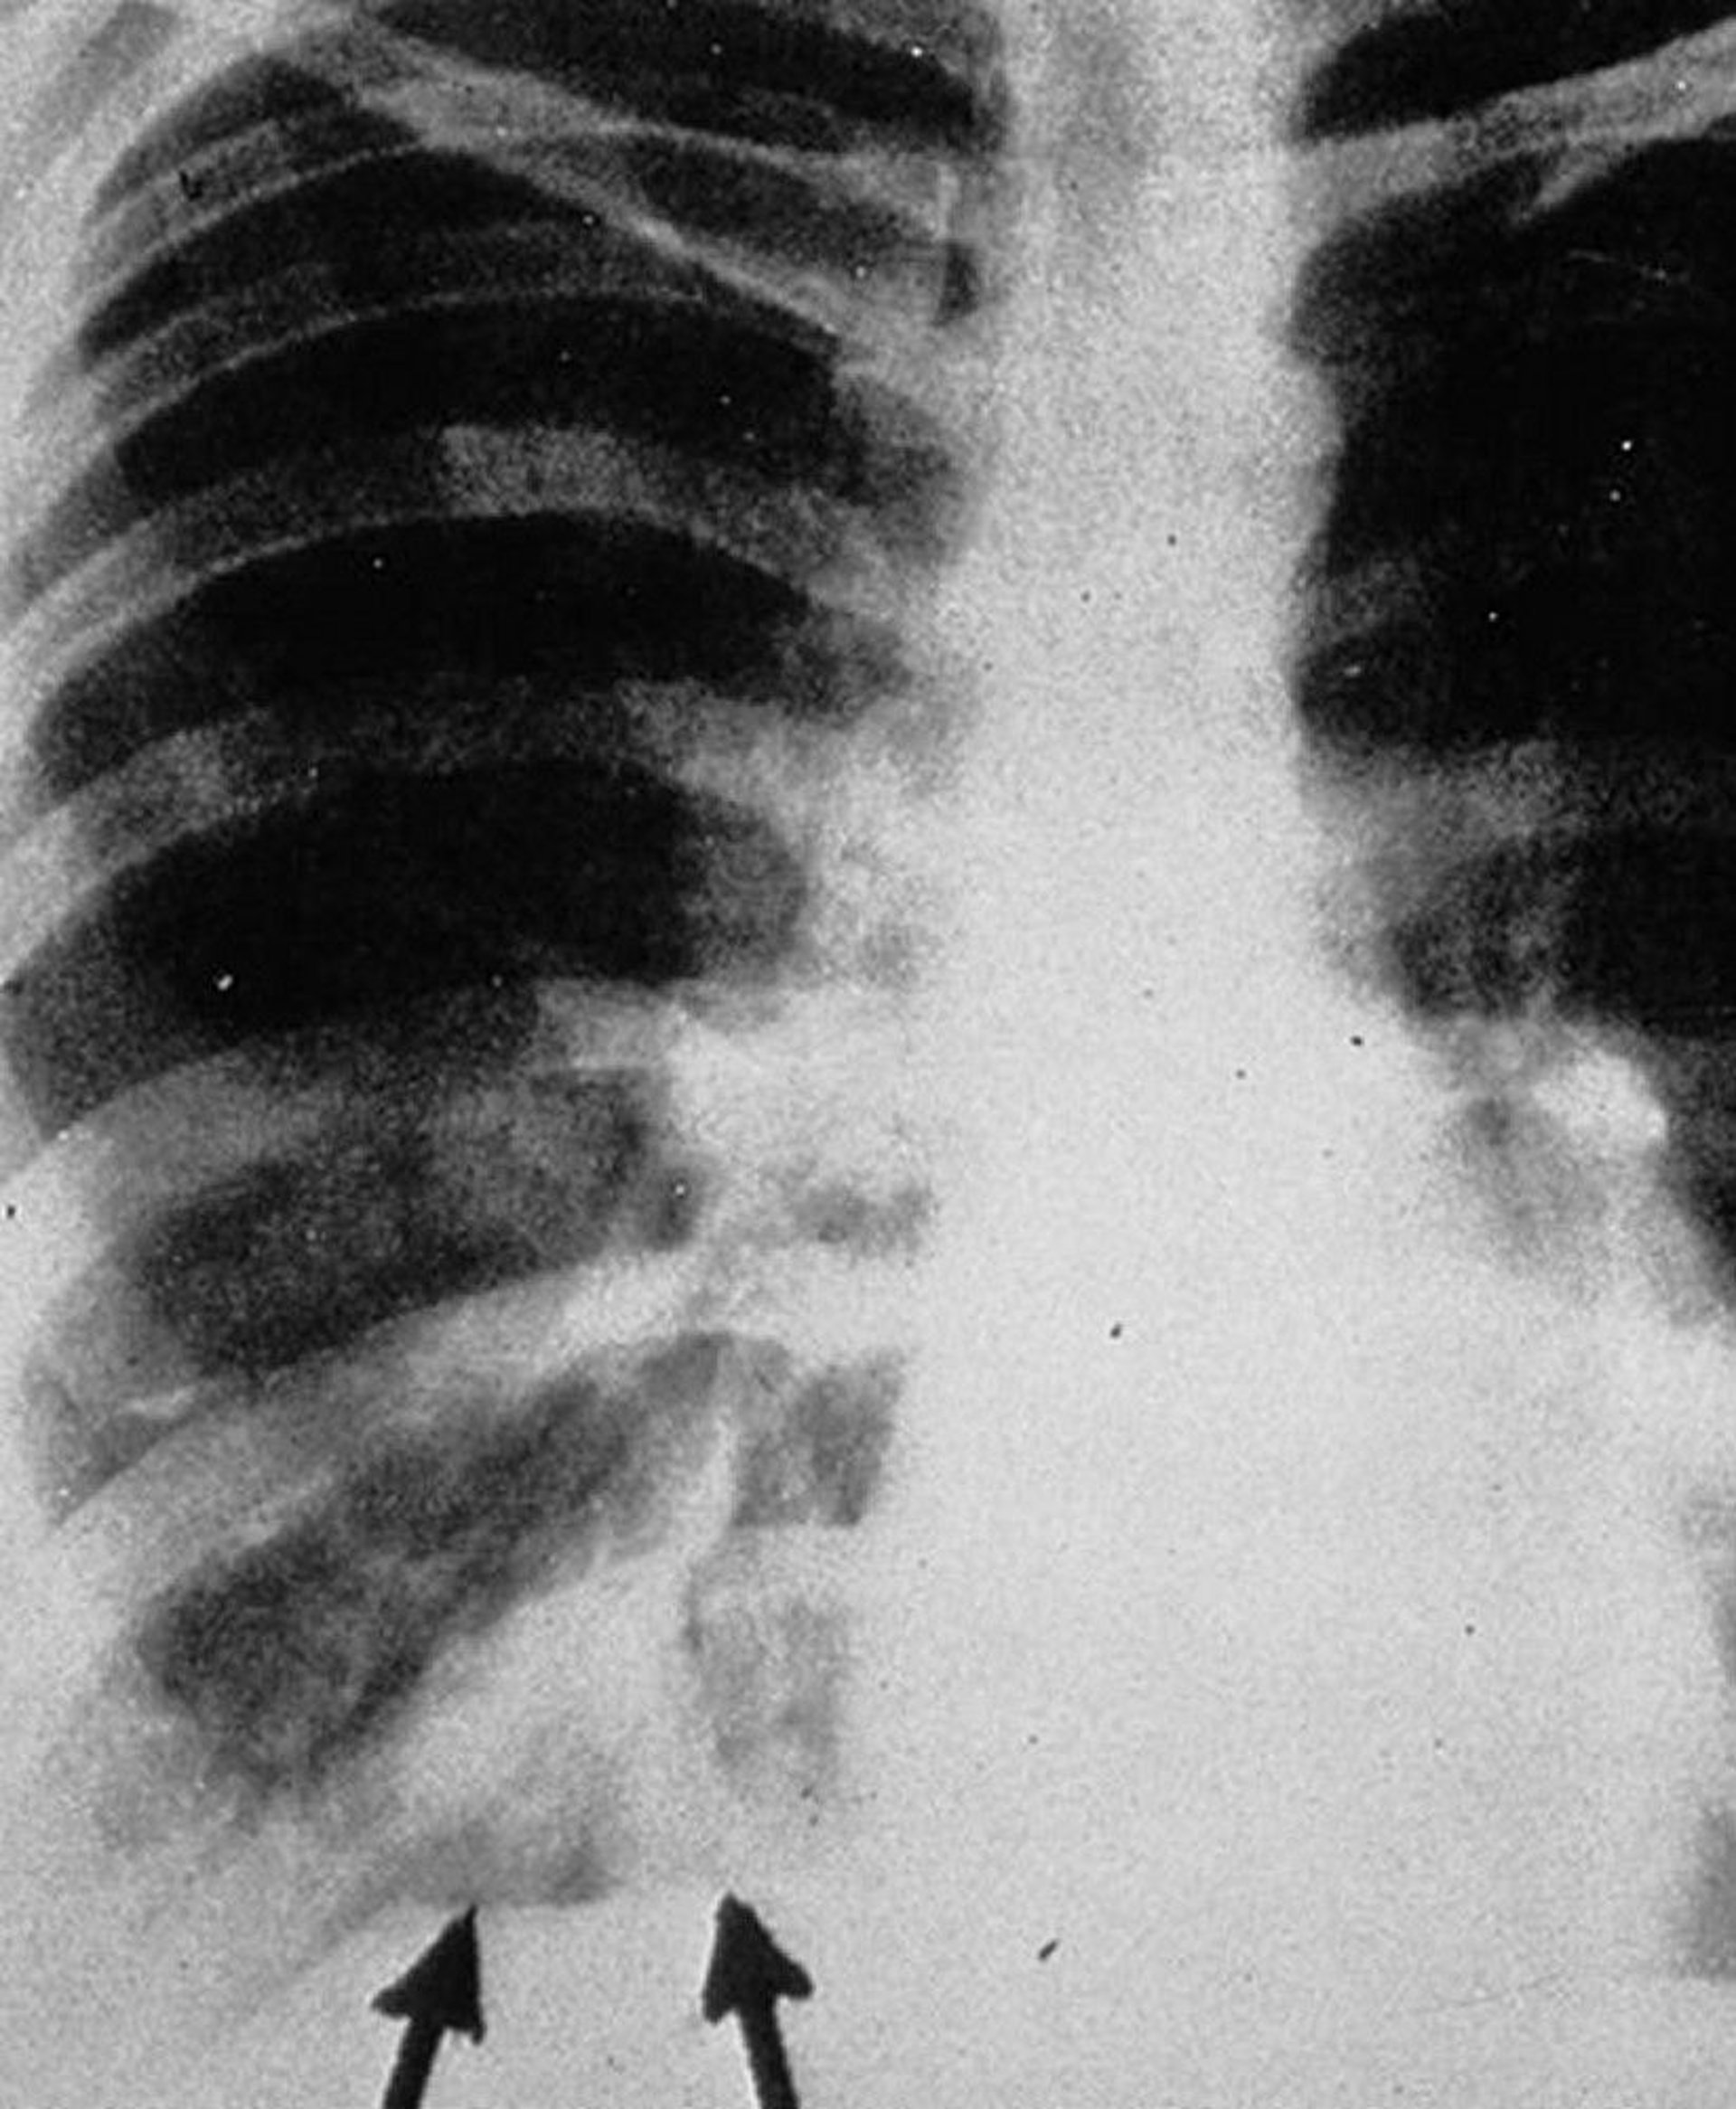

Posteroanterior chest radiograph shows "gloved finger" shadows (arrows), appearing as branched tubular densities that represent intrabronchial exudates with bronchial wall thickening.

By permission of the publisher. From Groll A, Walsh T. In Atlas of Infectious Diseases: Fungal Infections. Edited by GL Mandell and RD Diamond. Philadelphia, Current Medicine, 2000.